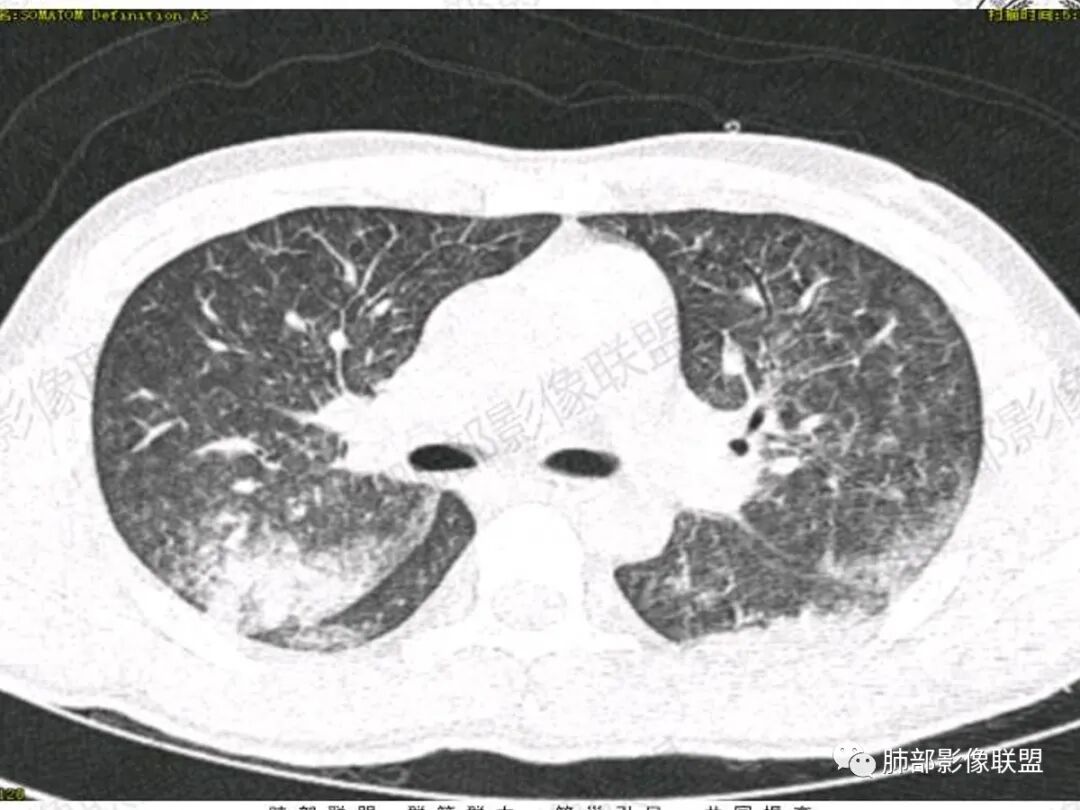

双肺上叶,下叶背段多发斑片状实变影,以胸膜下分布为主,部分重力作用,以背侧为主,部分小叶间质增厚,部分周围伴有散在磨玻璃影,边界欠清,临床急性病程,血象增及PCT明显增高,意识模糊,考虑:吸入性肺炎?鉴别:AHP?CEP?PCP

影像:两肺上叶小叶间隔增厚,斑片,腺泡结节,重力分布,下肺不累及

影像学提示肺水肿与肺泡腔液性渗出(小叶间隔增厚+实变+重力趋势),上叶显著。

双肺弥漫性病变以上肺,向心性,背部分布为主,肺动脉干无增粗,急性起病,典型的吸入性肺炎。

青年男性,气促7小时入院,意识模糊,白细胞及中性粒明显增高,PCT增高,CRP不高,心率快,体温正常,血压正常。胸部CT:双肺上叶小叶间隔光滑增厚,中轴间质增厚,弥漫性磨玻璃、多发斑片影,以上肺、背侧分布为主。影像表现考虑为肺水肿。病因:病史不支持肾功能衰竭、心源性、高原性肺水肿,无发热,似乎也不支持细菌、病毒、真菌等感染引起。吸入毒物?吸入水?

病灶的分布以上肺为主

确实要考虑吸入,倾向于吸入的是气体类的可能,因为朝上走

结合病史,最终诊断是 “急性烟雾吸入性肺损伤”,影像学表现主要是肺水肿及弥漫性肺泡损伤改变,因为烟雾气体吸入肺内分布以上肺显著,因此影像学表现也是累及上肺更明显。损伤因素包括大量一氧化碳 二氧化碳 一氧化氮等燃烧产生的有毒气体,也有烟雾粉尘颗粒对气道黏膜的损伤。